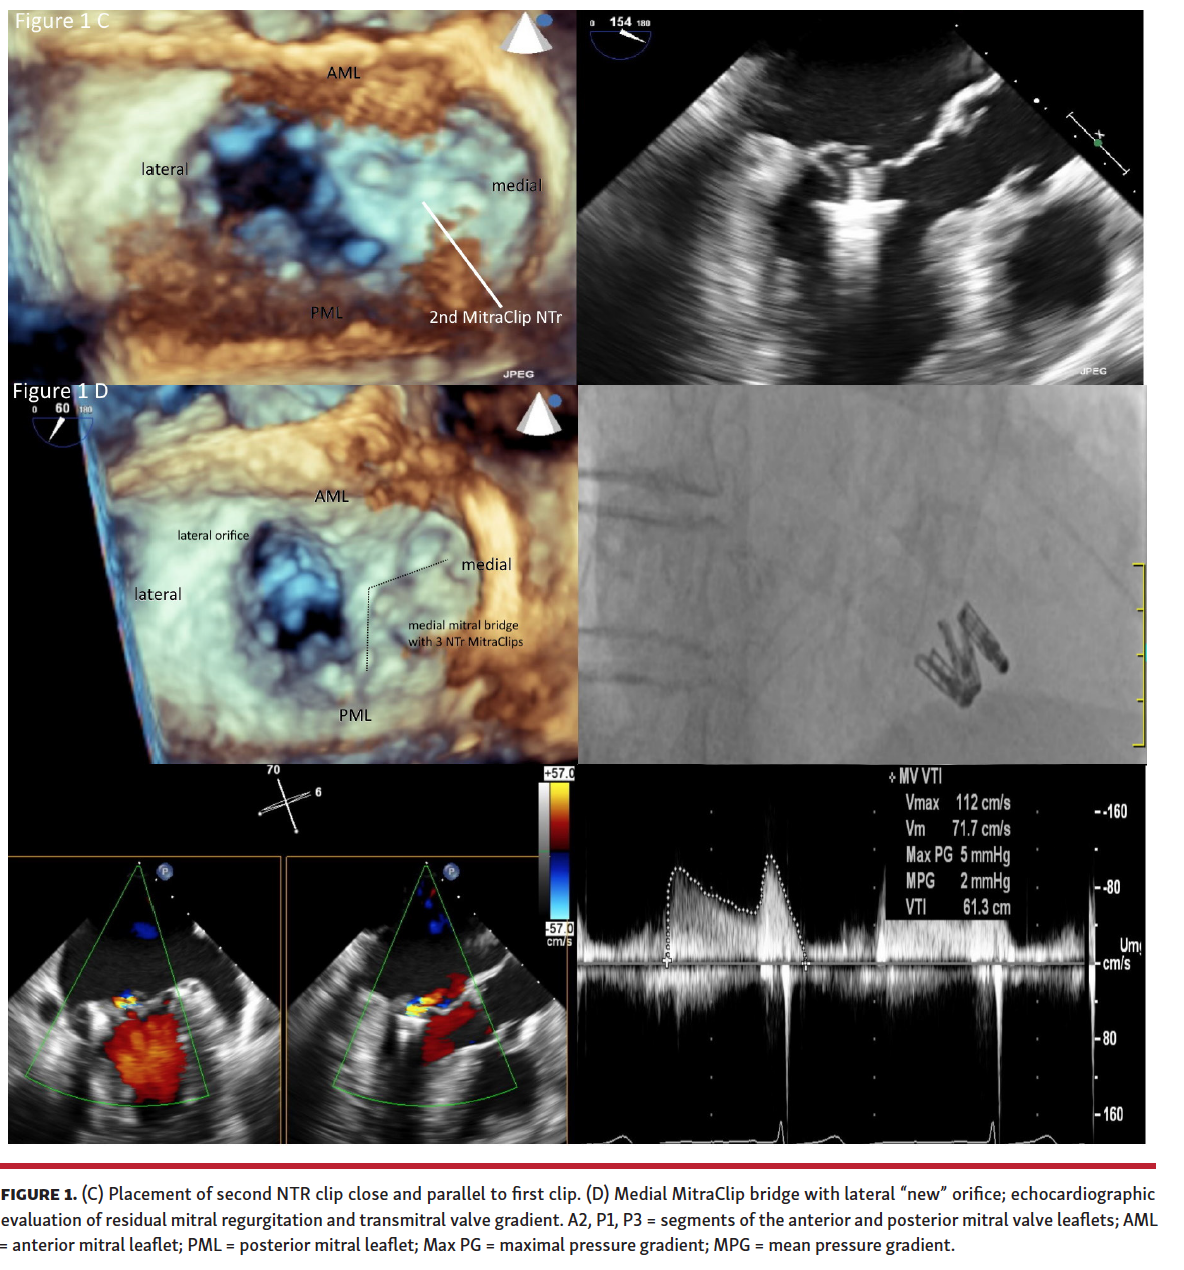

(3) The first medial clip stabilizes the prolapsing valve. We proceed more centrally, close and parallel to the first clip, optimizing stress distribution (Figure 1C).

(4) Evaluation of residual mitral regurgitation (MR; must be less than second degree) and transmitral valve gradient (must be <5 mm Hg) is performed to confirm the possibility/necessity of additional clips.

(5) Multiple MitraClips may be necessary to stabilize the prolapse (Figure 1D).

(6) A new coaptation line through MitraClip bridge minimizes the risk of residual MR, creating a new lateral orifice (Figure 1D).